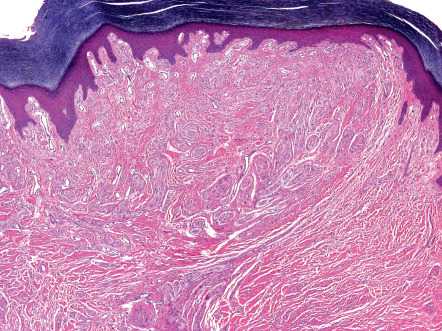

Solitary PENs are well-circumscribed, ovoid or round tumors located in the mid dermis, although some lesions may extend into the subcutis. The tumor appears encapsulated by a thick condensation of collagen fibers that surround it, and there is often some clefting from the adjacent dermis ( Fig. 115.5 ). The parenchyma is composed of interwoven fascicles of spindled cells. The fascicles are compactly and relatively uniformly arranged, separated only by clefts. There is no evidence of extensive fibrosis, inflammation, granulation tissue, degenerative changes or foreign bodies, in contrast to traumatic neuromas .

The nuclei of the spindle-shaped tumor cells are elongated and wavy with tapered ends, and they have an evenly basophilic chromatin pattern. Occasionally, a parallel arrangement of the nuclei is present, but, despite its name, distinct palisading or Verocay body formation is rare . There is no appreciable nuclear pleomorphism, and mitotic figures are scant or absent. Special stains show abundant axons in a variable pattern . The tumors of MEN 2B share some features with PEN but are not encapsulated and are multiple.